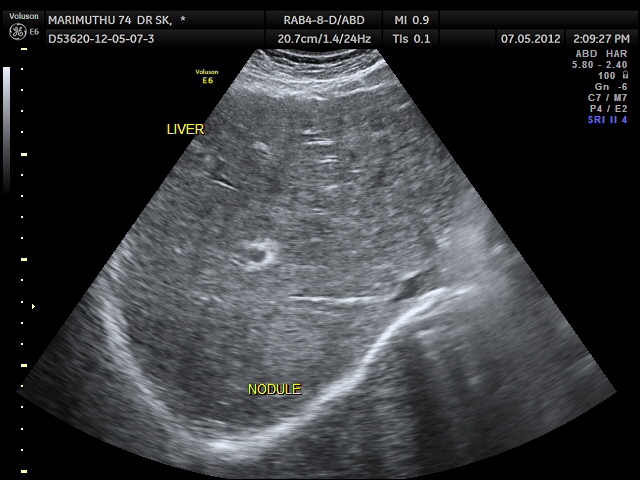

Please note that the ultrasound pictures of this patient are from our records. The PET CT images are done elsewhere at Chennai. They are reproduced here as they give the full picture of the clinical presentation.

This 74 year old gentleman has been coming to me for more than 10 years for mild systemic hypertension and hypothyroidism.He used to smoke cigars until a few years ago. 3 years ago he developed unexplained giddiness and on evaluation was found to have pituitary macroadenoma. Endocrine and neuro surgical consulatations were sought and he was on cabergoline and was doing very well. In April 2012 , he came for a routine review and was asked to continue his existing medications . One week later he came again with severe right upper quadrant pain and aversion to food. There was no history of cough in the recent past. He was advised an ultrasound scan of the abdomen and the findings are as below.

Extensive FDG avid hepatic metastases involving both lobes.